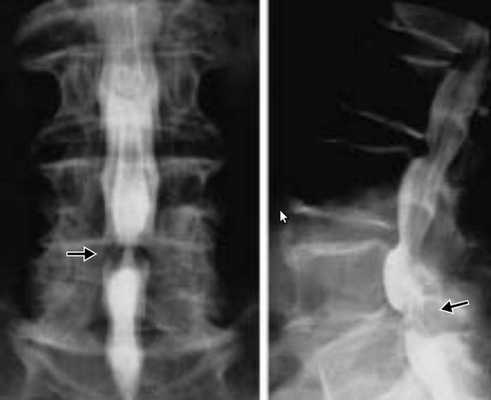

Магнитно-резонансная томография (МРТ) позволяет оценить состояние головного мозга, наличие свежих и старых ишемических очагов. В режиме МРТ ангиографии возможно без контраста оценить состояние шейных и внутримозговых отделов позвоночных артерий. С точки зрения визуализации артериальной патологии МРА уступает компьютерной томографии с ангиографией, однако не требует использовани контрастного вещества, что важно для пациентов с нарушением функции почек. На представленном изображении показана тромботическая закупорка левой позвоночной артерии (отсутствие контрастирование показано стрелкой).

"Золотым стандартом" для диагностики стеноза позвоночной артерии остается цифровая рентгеновская ангиография , хотя она и несет определенные риски осложнений и требует опытного специалиста для соблюдения технологии обследования. В нашей клинике ангиография позвоночной артерии проводится после принятия решения о эндоваскулярном вмешательстве (стентировании) с целью окончательной диагностики. Непосредственно во время исследования возможно проведение операции.